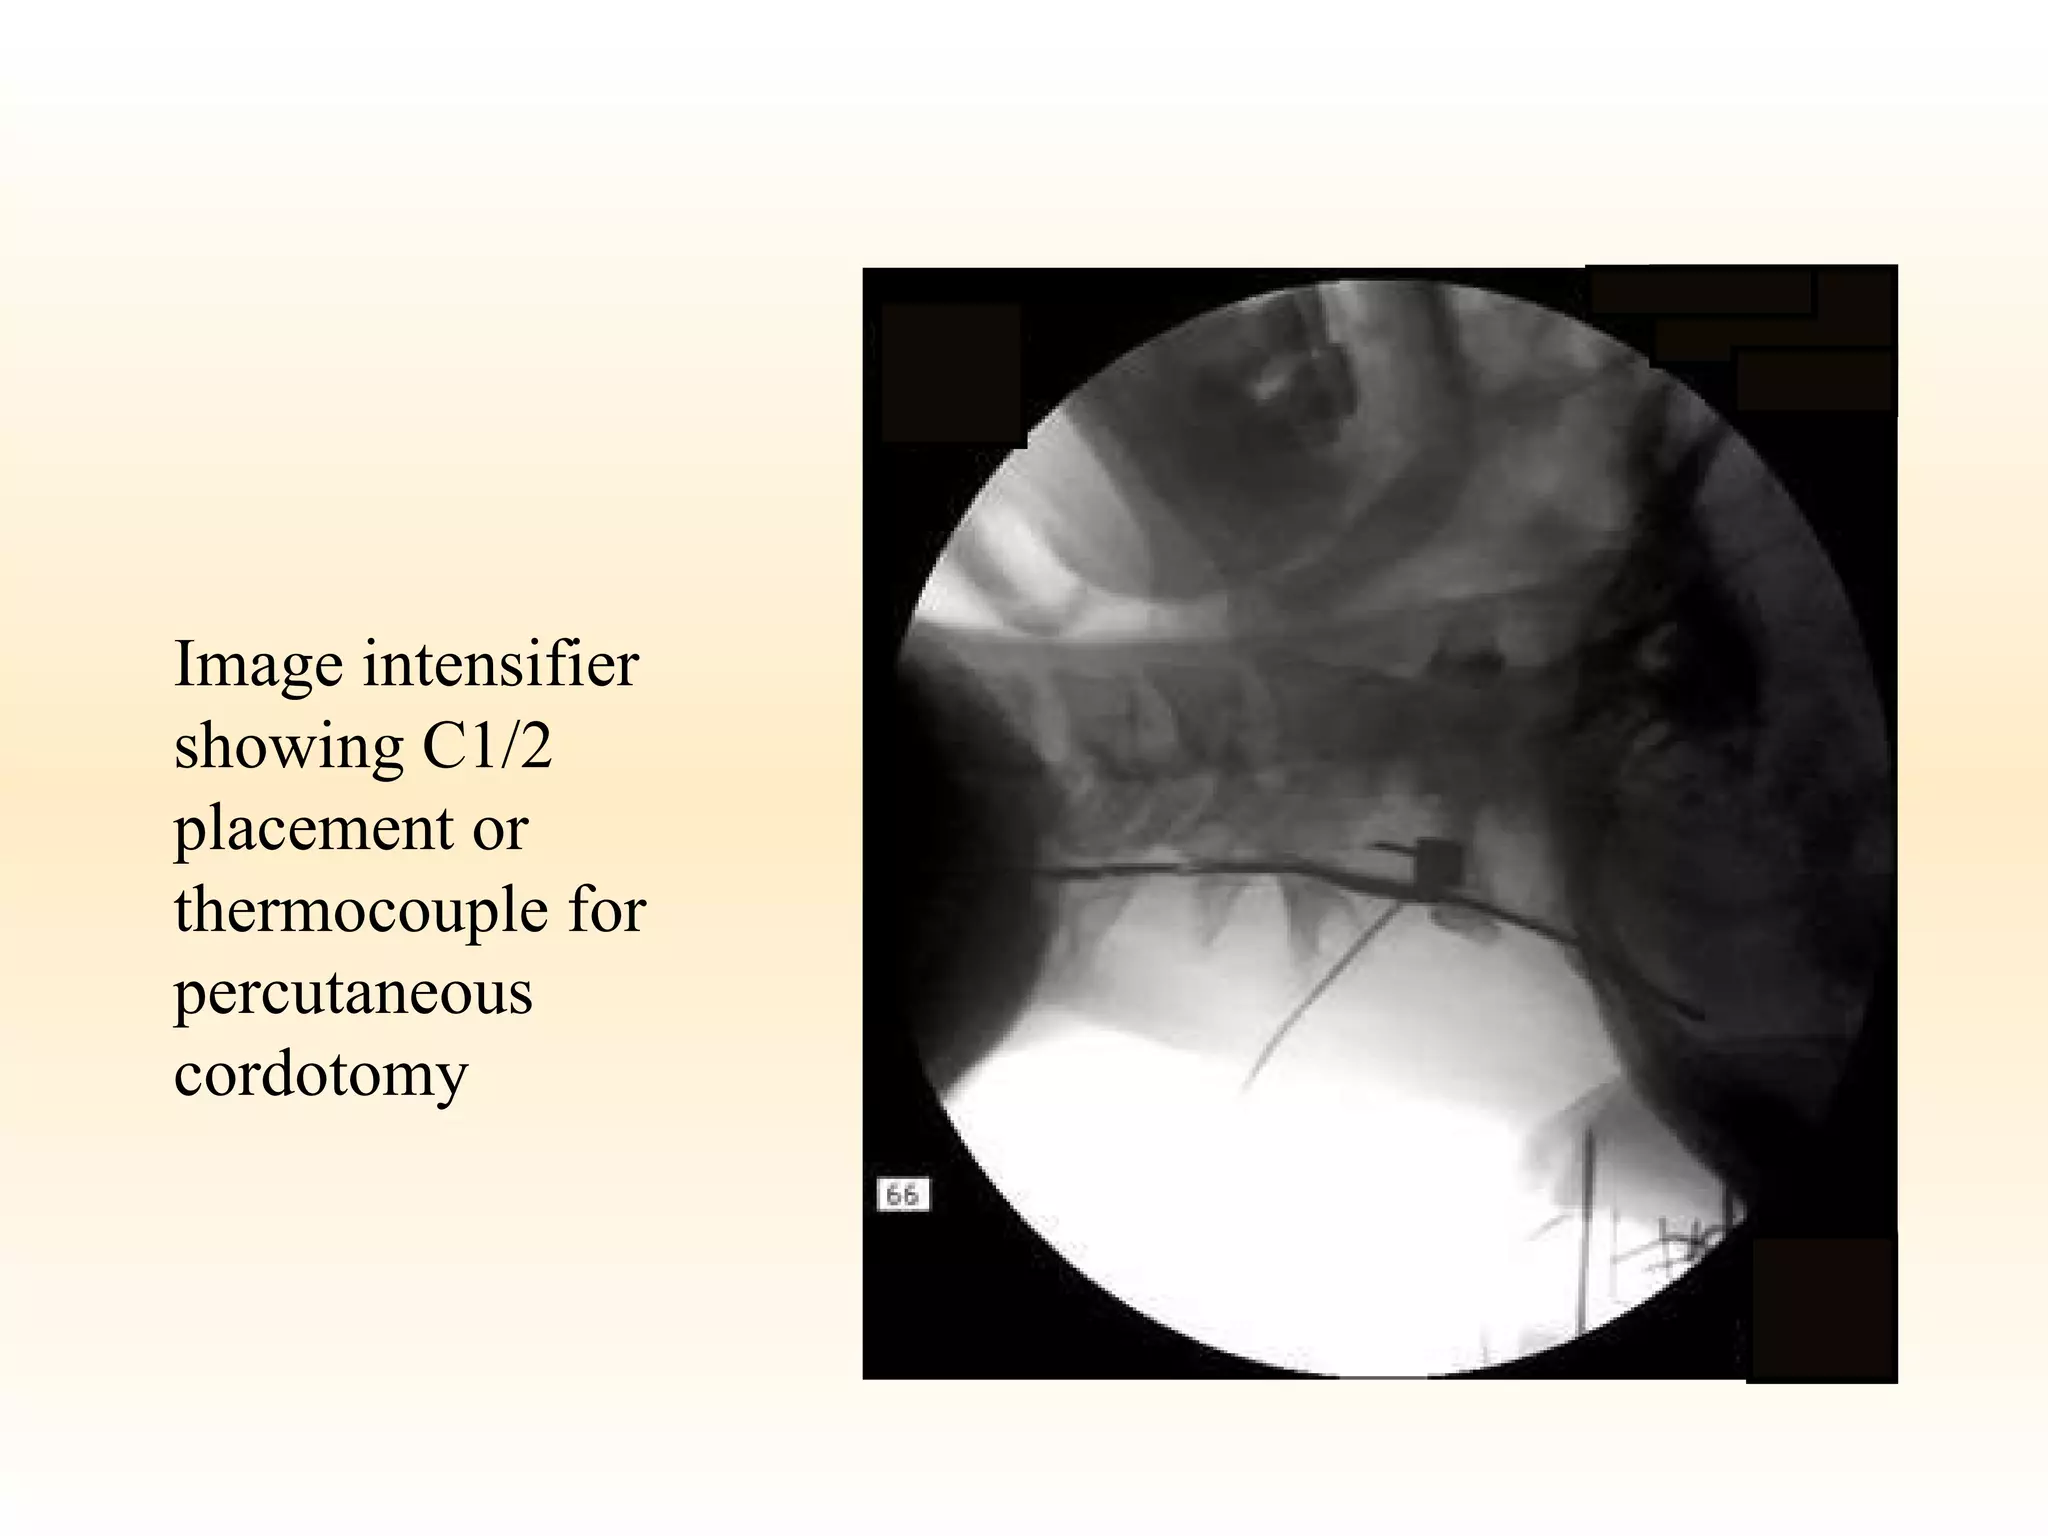

Anterolateral Cordotomy Thorax. 1999 Mar;54(3):238-41   P ercutaneous cervical cordotomy for the control of pain in patients with pleural mesothelioma. Interruption of spinothalamic tract within the spinal cord, usually performed as radiofrequency coagulation at C2

Cordotomy Only treats pain on one side of the body. Bilateral cordotomy can be performed, but although this will stop pain on both sides of the body it does not affect midline pain and is generally associated with a higher incidence of side effects.  Evidence level IV Percutaneous procedure is more commonly used, and is performed in the cervical region at C1-2. The highest level of analgesia obtainable is about C4 which corresponds to the shoulder. Neck pain does not normally respond. Special care is needed in patients with impaired lung function, as percutaneous cervical cordotomy may cause some reduction in the expansion of the lung on the side of the procedure. This is obviously important in patients with lung tumours. Cordotomy can provide complete analgesia in about 2/3 of patients. If a patient has widespread pain, but one location where it is not controlled by simple measures, then cordotomy may be useful in controlling that pain. The pain relief is not permanent, and the duration is variable. Pain relief will seldom last longer than one year in most patients.  Evidence level IV

Image intensifier showing C1/2 placement or thermocouple for percutaneous  cordotomy

Anterolateral Cordotomy Thorax.1999 Mar;54(3):238-41 P ercutaneous cervical cordotomy for the control of pain in patients with pleural mesothelioma. Interruption of spinothalamic tract within the spinal cord, usually performed as radiofrequency coagulation at C2

Cordotomy Only treatspain on one side of the body. Bilateral cordotomy can be performed, but although this will stop pain on both sides of the body it does not affect midline pain and is generally associated with a higher incidence of side effects. Evidence level IV Percutaneous procedure is more commonly used, and is performed in the cervical region at C1-2. The highest level of analgesia obtainable is about C4 which corresponds to the shoulder. Neck pain does not normally respond. Special care is needed in patients with impaired lung function, as percutaneous cervical cordotomy may cause some reduction in the expansion of the lung on the side of the procedure. This is obviously important in patients with lung tumours. Cordotomy can provide complete analgesia in about 2/3 of patients. If a patient has widespread pain, but one location where it is not controlled by simple measures, then cordotomy may be useful in controlling that pain. The pain relief is not permanent, and the duration is variable. Pain relief will seldom last longer than one year in most patients. Evidence level IV

Image intensifier showingC1/2 placement or thermocouple for percutaneous cordotomy